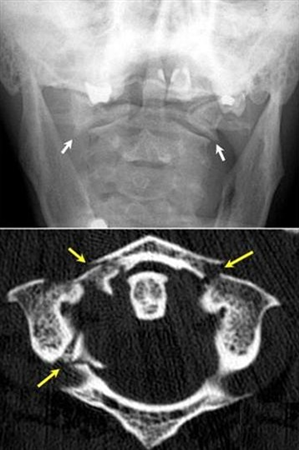

1. A 79-year old man falls sustaining a hyperextension injury to his neck. A lateral radiograph, CT scan and MRI are seen in Figures A through C. On motor examination, he has 3/5 strength in his deltoids, elbow and wrist flexors and extensors. He has 4/5 strength in his hip flexors, knee flexors, extensors, ankle dorsiflexors and plantarflexors. Sensation is preserved in both his upper and lower extremities as well as his sacral segments. Injury to which of the following tracts contributes greatest to his motor function deficits?

FIGURES: A

B

C

DISCUSSION: The clinical scenario describes a patient with central cord syndrome, resulting in an injury to his lateral corticospinal tract. Figures A through C show a spondylytic spine with central narrowing and CSF effacement that is worse at the C4-5 level. The lateral corticospinal tract is the main descending motor tract (Illustration A). Its anatomic position places the upper extermity motor tracts at greater risk than the lower extremity tracts. As such, injury to the lateral corticospinal tract is characterized by upper greater than lower extremity involvement and motor deficits being more pronounced than sensory deficits.